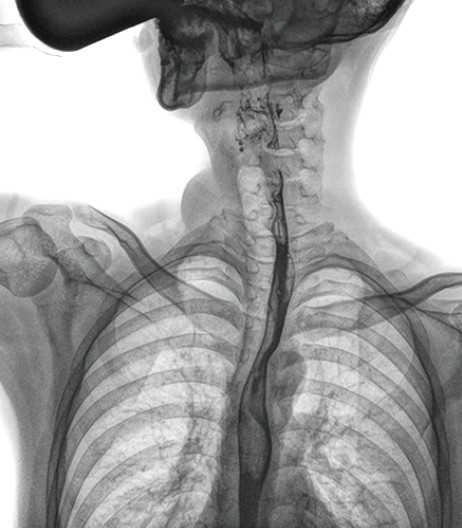

食管造影是食管病变的基本检查方法,可以发现食管癌的特征性改变——食管粘膜的中断和破坏,病人常感觉吞咽障碍,此特征在临床中最常见,也是早期食管癌的典型表现。一般伴随的特征有管壁充盈缺损、龛影、软组织块影、食管腔狭窄等;在透视下还可看到食管壁僵硬、蠕动缓慢等。

动态DR能够实现大幅面透视,瞬时高清点片等。在食管造影检查中,由于吞咽钡剂后,造影剂流速非???,在一个大幅面上方便观察食管的病变。瞬时点片,可以实时捕捉到病变部位的影像,从而可以快速做出诊断。普利德多功能动态DR拥有17×17英寸超大视野,一次曝光即可显示整个食管,更方便观察食管的病变,确定病变的范围,对诊断和治疗有重要参考价值。

与过去的数字胃肠机比较,动态DR图像分辨率高,对食管的全景观察,局部粘膜破坏、中断,管腔狭窄以及病灶范围的显示清晰度明显更优。

上消化道造影高清图像